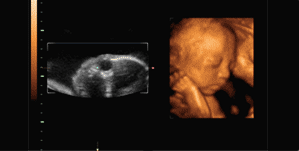

四维彩超是目前世界上最先进的彩色超声设备,是采用三维超声图像加上时间维度参数,更直观更清晰地呈现胎儿在宫内的动态图像,多方位、多角度地观察胎宝宝的生长发育情况,还能够对孕期潜藏的各类疾病进行精确检测。

但检查受胎儿体位、不同孕期、胎盘、羊水等诸多因素影响,因此建议孕妈妈在以下几个孕期内检查较好,最佳时期为12-30周(获取面部及内脏结构图像的最佳时间是20-28周)。

▪第三次检查可于孕28周左右进行。

此期胎儿皮下脂肪较以上饱满,面部表情也比较丰富,胎儿各个部位较前期更加清晰,不仅对以上各类畸形的诊断更加明确,而且胎儿面部的各种表情,如吃手指、喝羊水、打呵欠、哭闹等表情清晰可见。